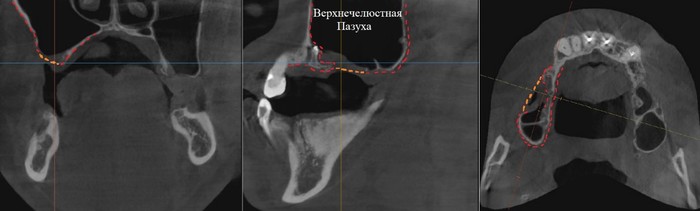

Согласитесь, не особо эстетично. Ортопантомограмма:

Фрагмент компьютерной томографии (вид сбоку):